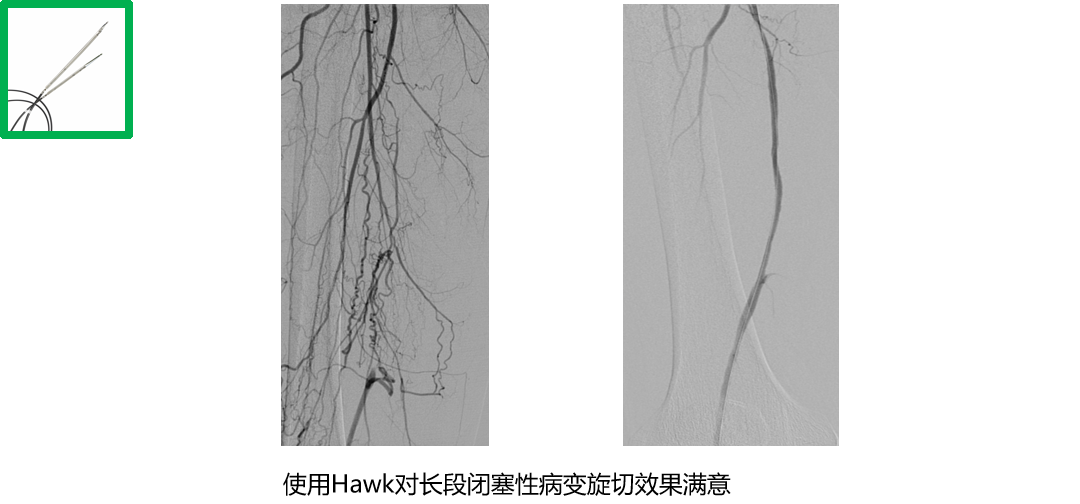

长期严重钙化

长段严重钙化病变因钙化范围广、质地坚硬,常规扩张治疗易出现血管撕裂、夹层等并发症,且管腔开通效果不佳。定向斑块旋切术凭借 “精准切削、靶向清除” 的核心优势,成为这类复杂病变的优选治疗方案,为临床破解长段钙化难题提供了高效路径。

★ 定向斑块旋切术

无限流性夹层的发生

避免支架植入